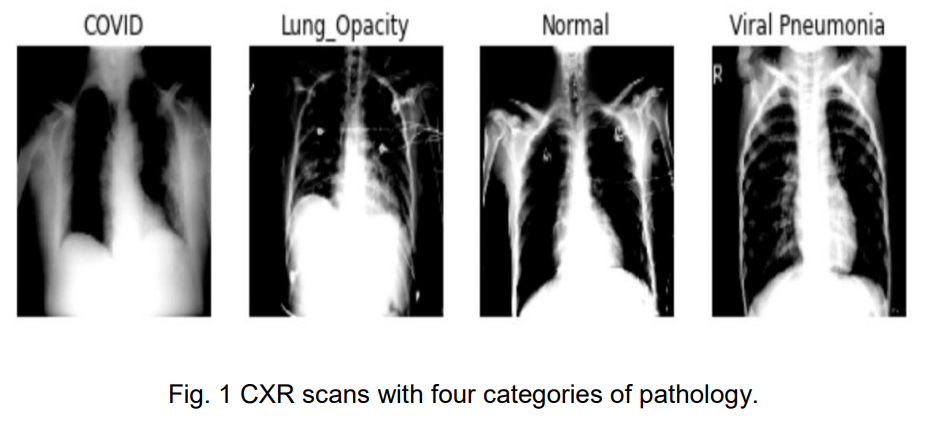

胸部X射线在Covid 19的识别和诊断中发挥了重要作用。我们在这个项目中的目标是能够对含有Covid 19、病毒性肺炎、肺部不透明和正常图像的不同胸部X光图像进行分类。我们使用了CNN架构和不同的预训练模型。使用ResNet 18架构获得了最佳结果,准确率为94.1%。我们还注意到,在AlexNet的情况下,GPU的执行时间是最佳的,但需要我们注意的是,预训练模型的收敛速度比从头开始训练CNN快得多。